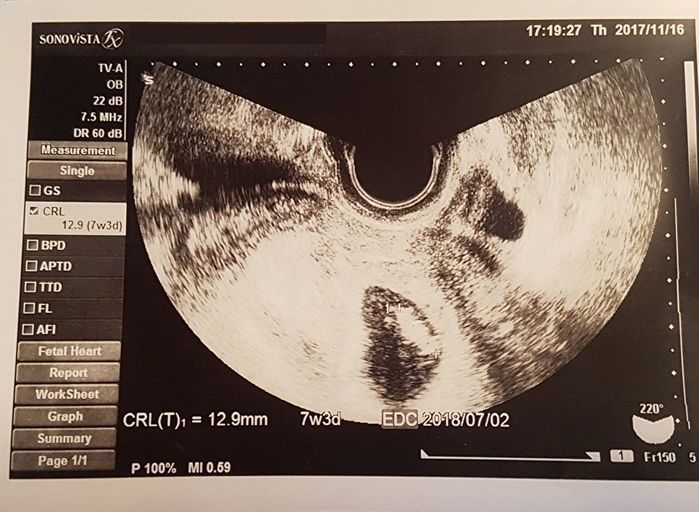

妊娠7週目 つらい体験の後の小さな命

大好きなお菓子を食べてもおいしくないし、熱っぽいと感じて産院へ行った結果、妊娠が判明。頭と胴体と足がかろうじて分かれているくらいの我が子。

「すごく小さい…、でも生きている」と、うれしくて涙がこぼれました。家族の不幸があったばかりだったので、新しい命が芽生えたことに感無量でした。しかし、妊娠したことをパートナーに告げると、産むのを反対されてしまいました。